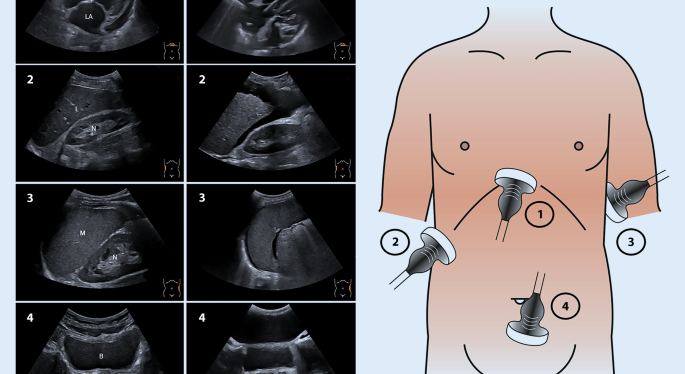

Abdomen-Sonographie (Bauchultraschall)

Mit dem Bauchultraschall können innere Organe wie Leber, Gallenblase, Nieren, Milz, Bauchspeicheldrüse und große Blutgefäße schonend untersucht werden. So lassen sich Entzündungen, Steine, Zysten oder Durchblutungsstörungen frühzeitig erkennen – völlig schmerzfrei und ohne Strahlenbelastung.